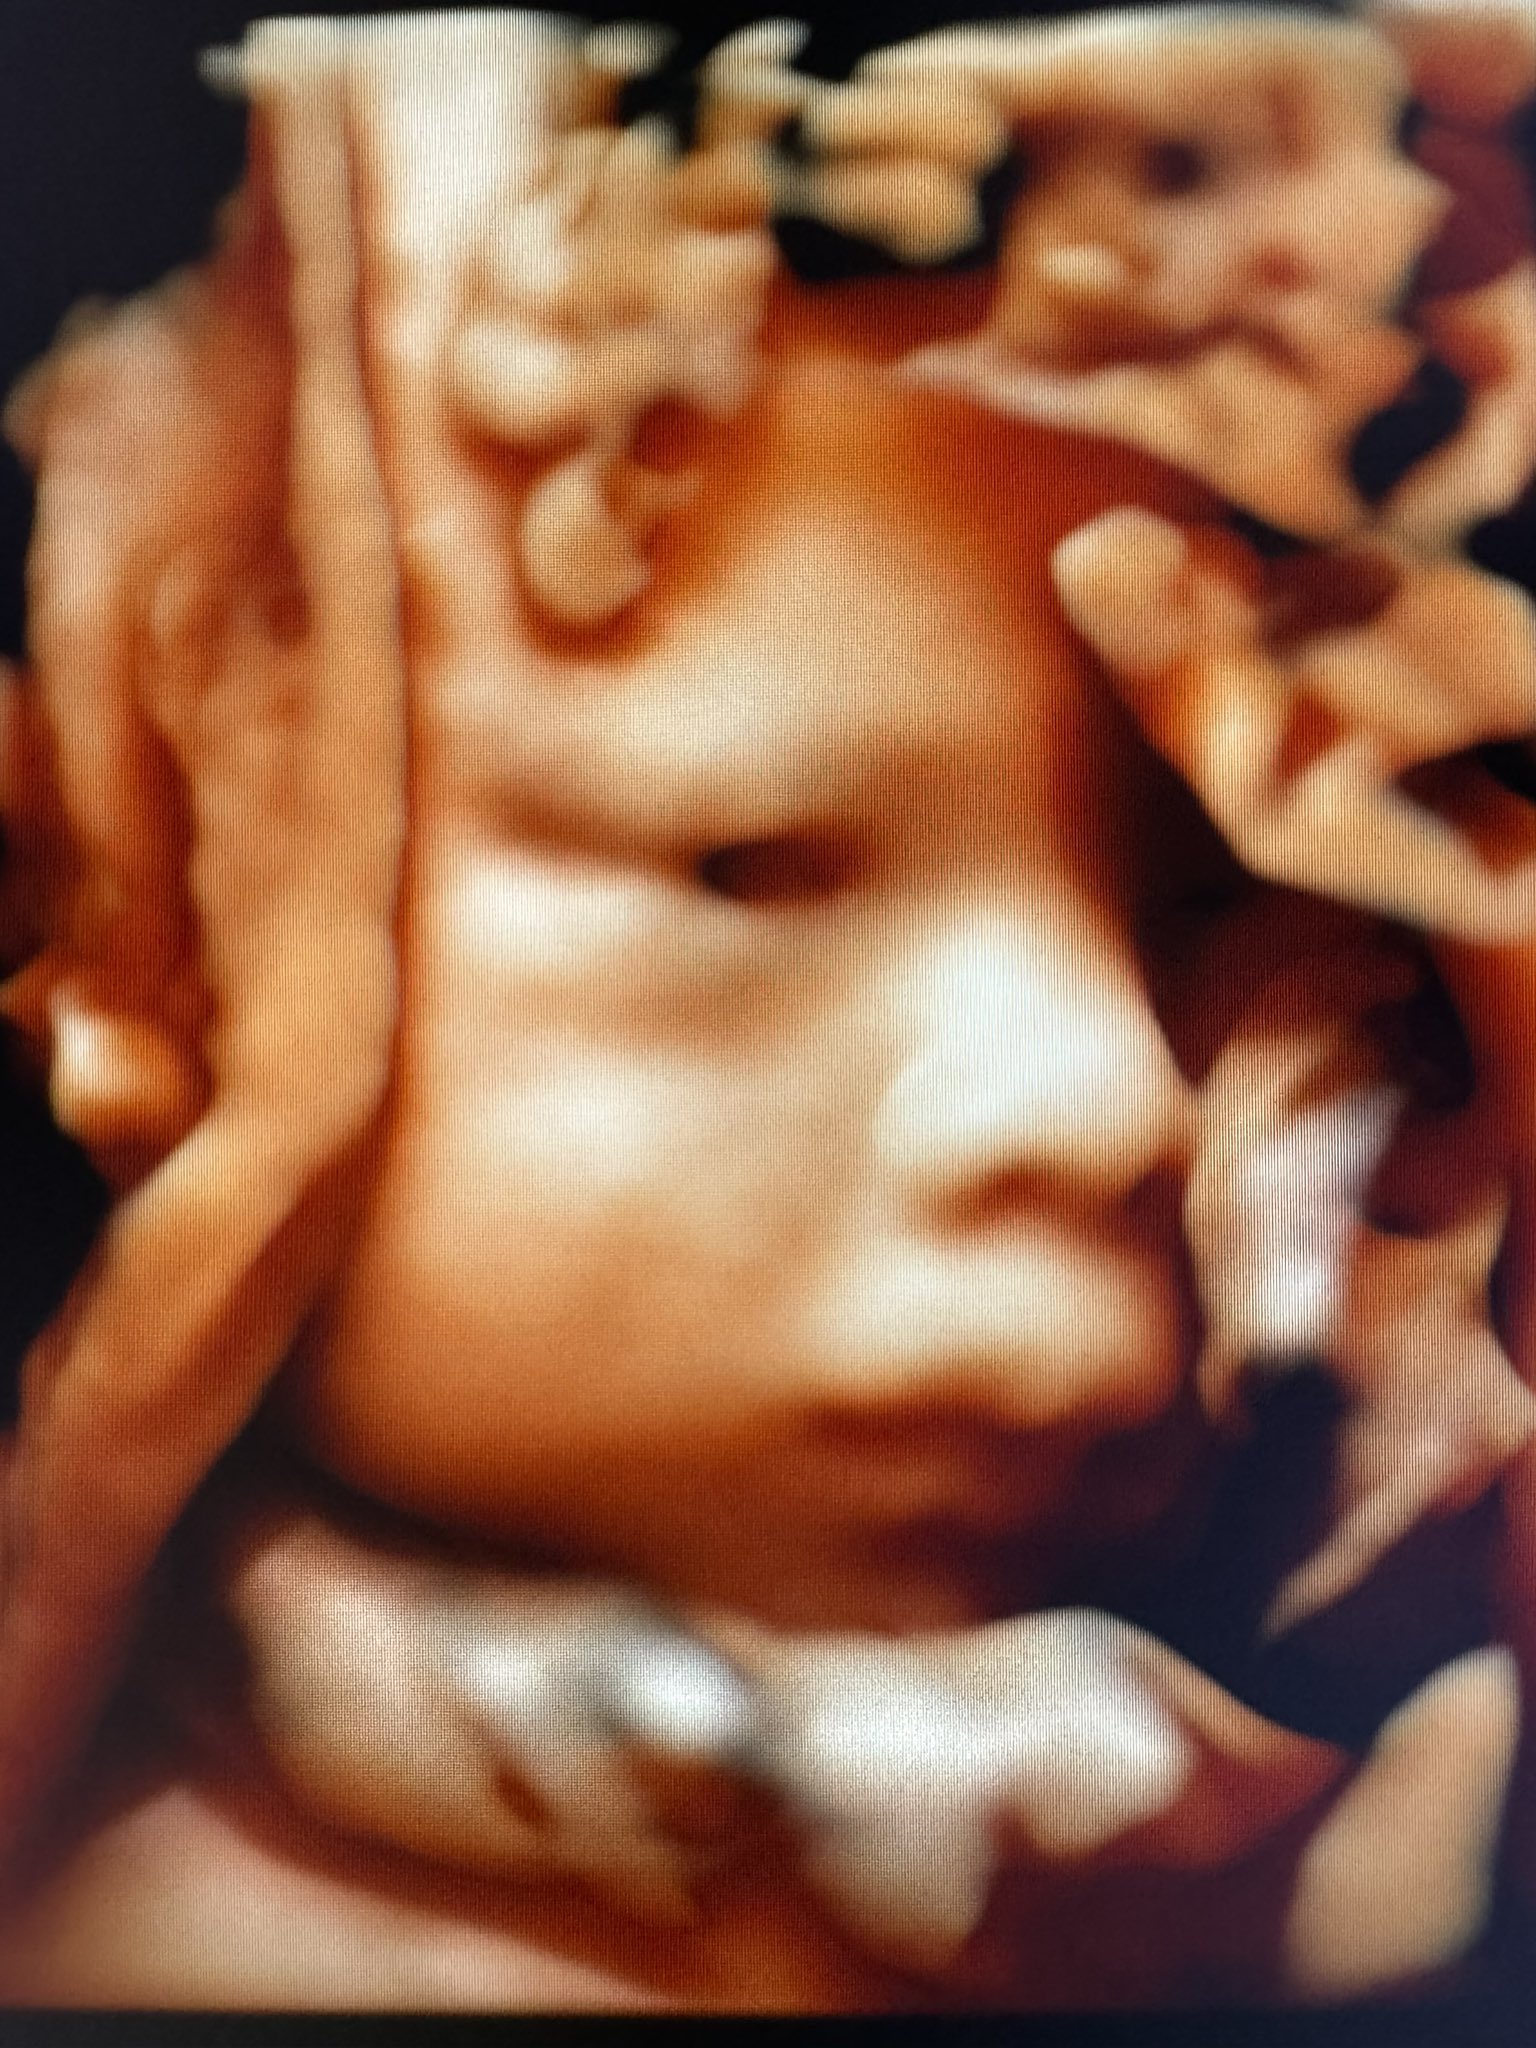

すんごい目力の赤ちゃんの写真撮れた👀(妊婦さんに投稿の許可をいただきました) https://t.co/QXd7x09Qbi

@mihyonsong 初めて目開いてるの見ました!👀羊水の中でも目開けられるんだ?👀

@mii_bb21 真っ暗なはずですけどねー

@mihyonsong すごい👀こんなにはっきり写ってるの初めて見ました!何かの表紙になってほしいです💕

@oraorade59 黒目まで見えるのはなかなかないです!